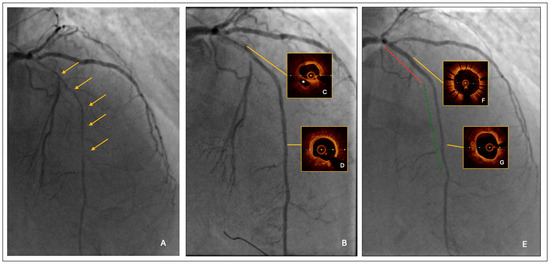

CAG was performed using the left radial artery access and with an adequate peri-interventional factor substitution, under the supervision of a hemophilia specialist. It showed a long severe critical stenosis of the left anterior descending artery (LAD) (Figure 1A). Given the clinical complexity and the severity of the CAD, the patient was evaluated by the local heart team, along with the hemophilia expert. Although the operative surgical risk was low (EuroSCORE II = 4% and STS Risk Score = 2%, respectively), taking into account the relevant comorbidities and also the low-income family backup, the heart team established PCI to be more appropriate than surgical approach in this specific case.

Lesion predilatation by a semi-compliant balloon, sized 1:1 to the reference vessel diameter; it was 2.0 mm at the distal segment and increased progressively up to 3.0 mm at the proximal segment, respectively. After lesion predilatation, the result was optimal in the middle-distal LAD, but suboptimal in the proximal segment, where a long linear dissection was observed (Figure 1B).

Intravascular imaging by optical coherence tomography (OCT) confirmed an adequate overall luminal gain and confirmed the presence of a large linear dissection in the proximal LAD, with significant residual stenosis and a moderate burden of calcium (Figure 1C,D).

The procedure was completed by a 2.25/20 mm and 2.5/25 mm drug-coated balloon (DCB) angioplasty of mid-distal LAD and by proximal LAD stenting using a 3.0/33 mm polymer-free Biolimus eluting stent.

The final result was satisfactory (Figure 1E); furthermore, the post-PCI OCT confirmed an acceptable minimal lumen area distally (A = 4.2 mmq) and an adequate stent apposition proximally, with the minimal stent area as high as 8.6 mmq. The total treated segment length was 73 mm (stent + DCB = 33 mm + 40 mm) (Figure 1F,G).

Figure 1. (A) Long severe critical stenosis of LAD. The orange arrows indicate the long segment of severe critical stenosis of LAD. (B) Angiographic result after lesion predilatation by semi-compliant balloons. (C) Pre-PCI OCT: Proximal linear dissection. The * indicates the false lumen of the proximal LAD linear dissection. (D) Pre-PCI OCT: Adequate distal luminal gain. (E) Angiographic result after PCI with DES (red line) and DEB (green line). (F) Post-PCI OCT: Optimal DES apposition. (G) Post-PCI OCT: Good distal luminal gain after DEB.